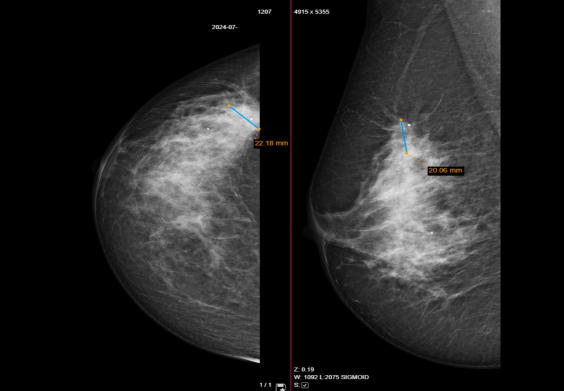

患者,55岁,女性,已绝经,无乳腺癌家族史。病理报告示:浸润性乳腺癌非特殊类型(NST),2级、ER 90%、PR 40%、HER2(1+)阴性、Ki-67 40%、cT2(23mm)N2M0,IIIA期。乳腺钼靶提示右乳约20mm肿瘤病灶。PET-CT提示右乳16.98*13.96mm代谢增高,可疑原发病灶;右腋窝2枚淋巴结代谢增高,考虑转移。

PET-CT提示右乳16.98*13.96mm可疑病灶,右腋窝2枚淋巴结可疑转移